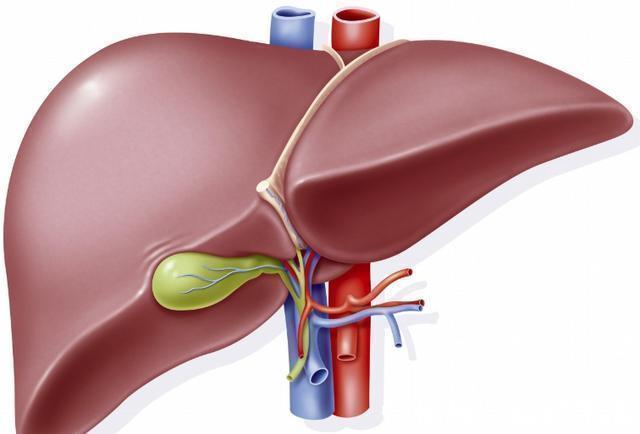

肝脏是人体的解毒器官,而且还负责一部分的消化和造血功能,被称之为五脏之首。然而就是这样一个重要的器官,内部并没有痛觉神经,所以当他出现问题时,并不容易被发现,养肝工作也就格外重要了,经过了一个晚上的代谢,早上养肝是十分重要的。

营养专家说:早上养肝最佳,多吃这3种食物,肝脏或会更健康